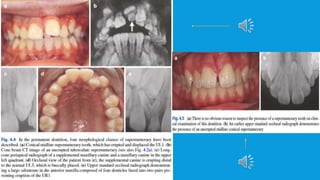

 In deciduous teeth they’re either of normal morphology or conical.

In permanent dentition, there’s more variability and four

morphological classes have been described: conical, tuberculate,

supplemental and odontomes. Each characterized by particular

features.

 The conical type is the most frequently observed class, followed by

tuberculate and supplemental.The frequency of odontomes is less

clear, and in some studies it isn’t considered as supernumerary.

 Morphology is also related to the likelihood of a supernumerary to

erupt. Studies have shown that the supplemental type is most likely

to erupt followed by conical and tuberculate.

Their presence may have no effect on the developing

dentition and can be a chance finding when a patient

first presents for orthodontic treatment.

However, in other instances, a variety of effects may be

seen including displacement, crowding, dilacerations,

root resorption, cystic change and nasal cavity eruption.

However, pathology is rare and the complication seen

most frequently is delayed eruption of an incisor.